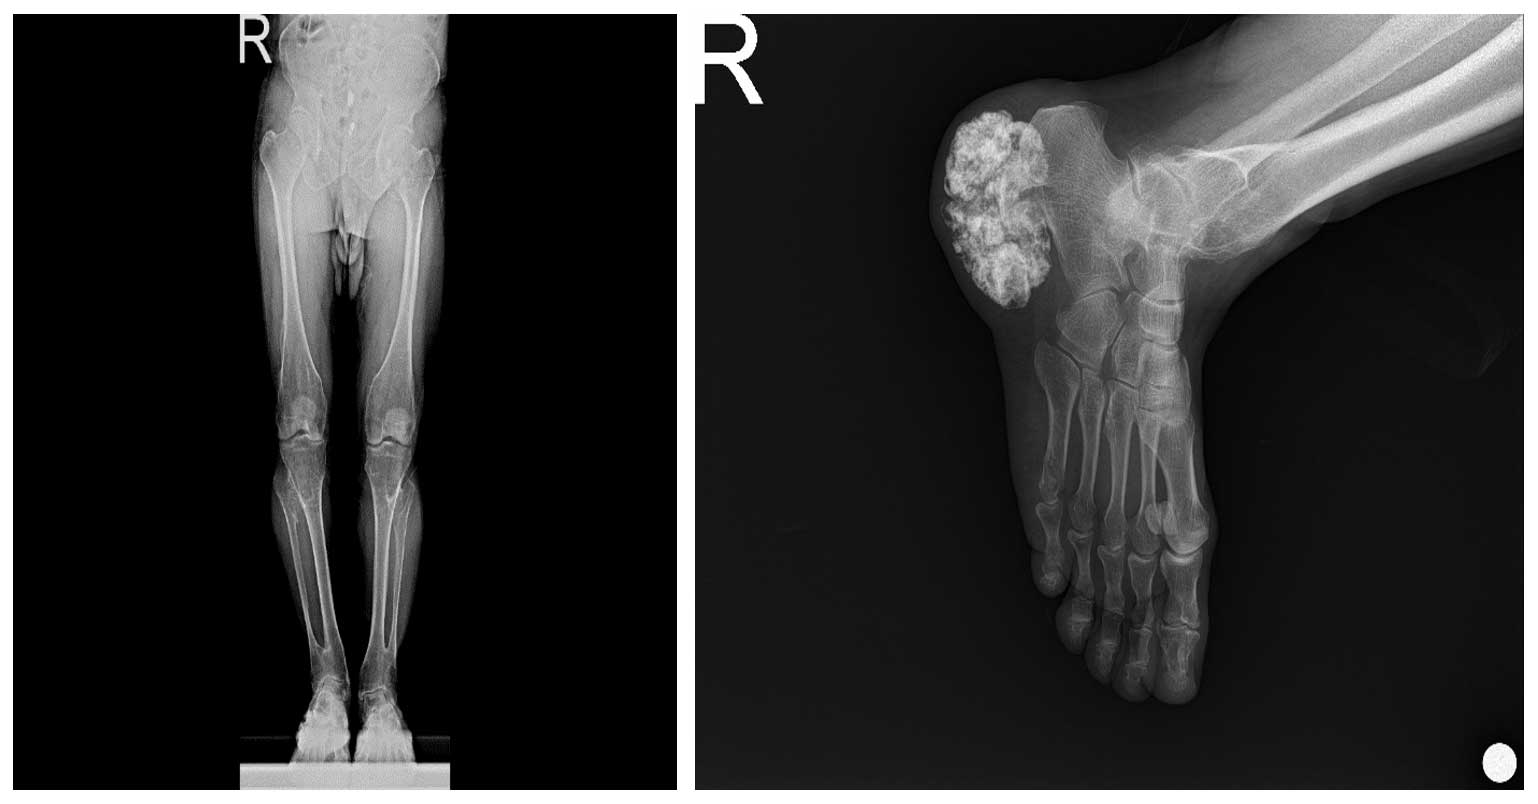

Ameliyat Sonrası: Röntgende tümörün çıkarıldığı görülmekte.